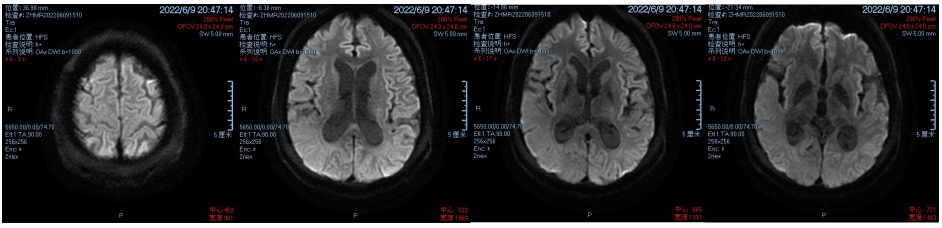

48岁男性病例,有夜尿病史,近5个月因膀胱排空不全症状加重入院治疗。2020年11月,患者逐渐出现头疼、头晕、记忆力下降、视力下降等不适症状,影像学检查结果如图1所示。随着病情发展,患者还出现癫痫、焦虑等症状,夜尿更为频繁;2022年8月,患者出现排尿时间延长、排空不完全、难以区分尿便等症状,皮肤活检可见包涵体样结构,遗传分析证实了NIID诊断。2022年9月,泌尿系彩超显示双侧输尿管扩张;2023年2月,彩超显示双肾积水,残余尿增加。

图1 影像学检查结果:大脑多个脑区存在异常